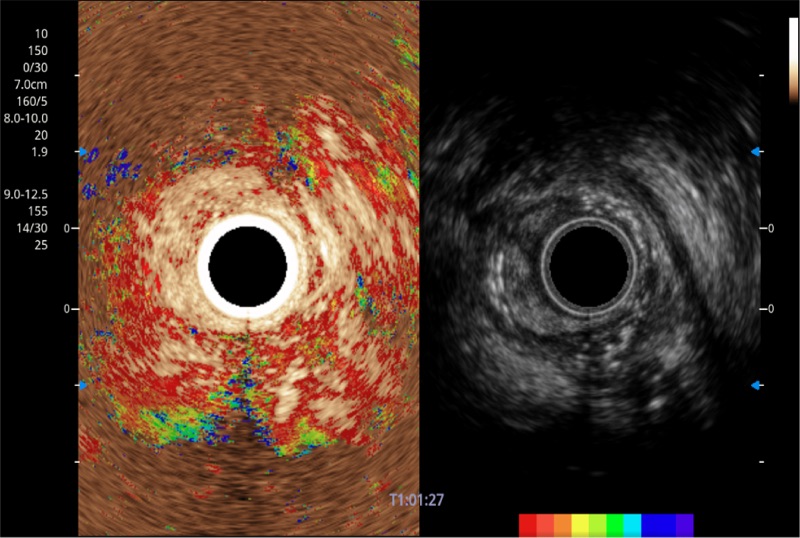

具有四种造影成像效果

食管内间质瘤清晰显像

清晰显示胆总管及周围血管分布